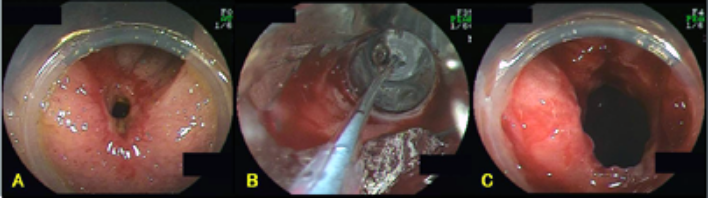

早期大腸癌に対するESD

1.直腸に認められたφ7cmの病変(左:通常観察、右:色素内視鏡観察)

2.当科が開発した先端細径透明フード(STフード)とヒアルロン酸ナトリウム局注液を使用して、内視鏡下に電気メスで病変を剥離していきます。

3.病変を取り去った後の直腸と切除標本。病変部の大きさはφ8cmでした。